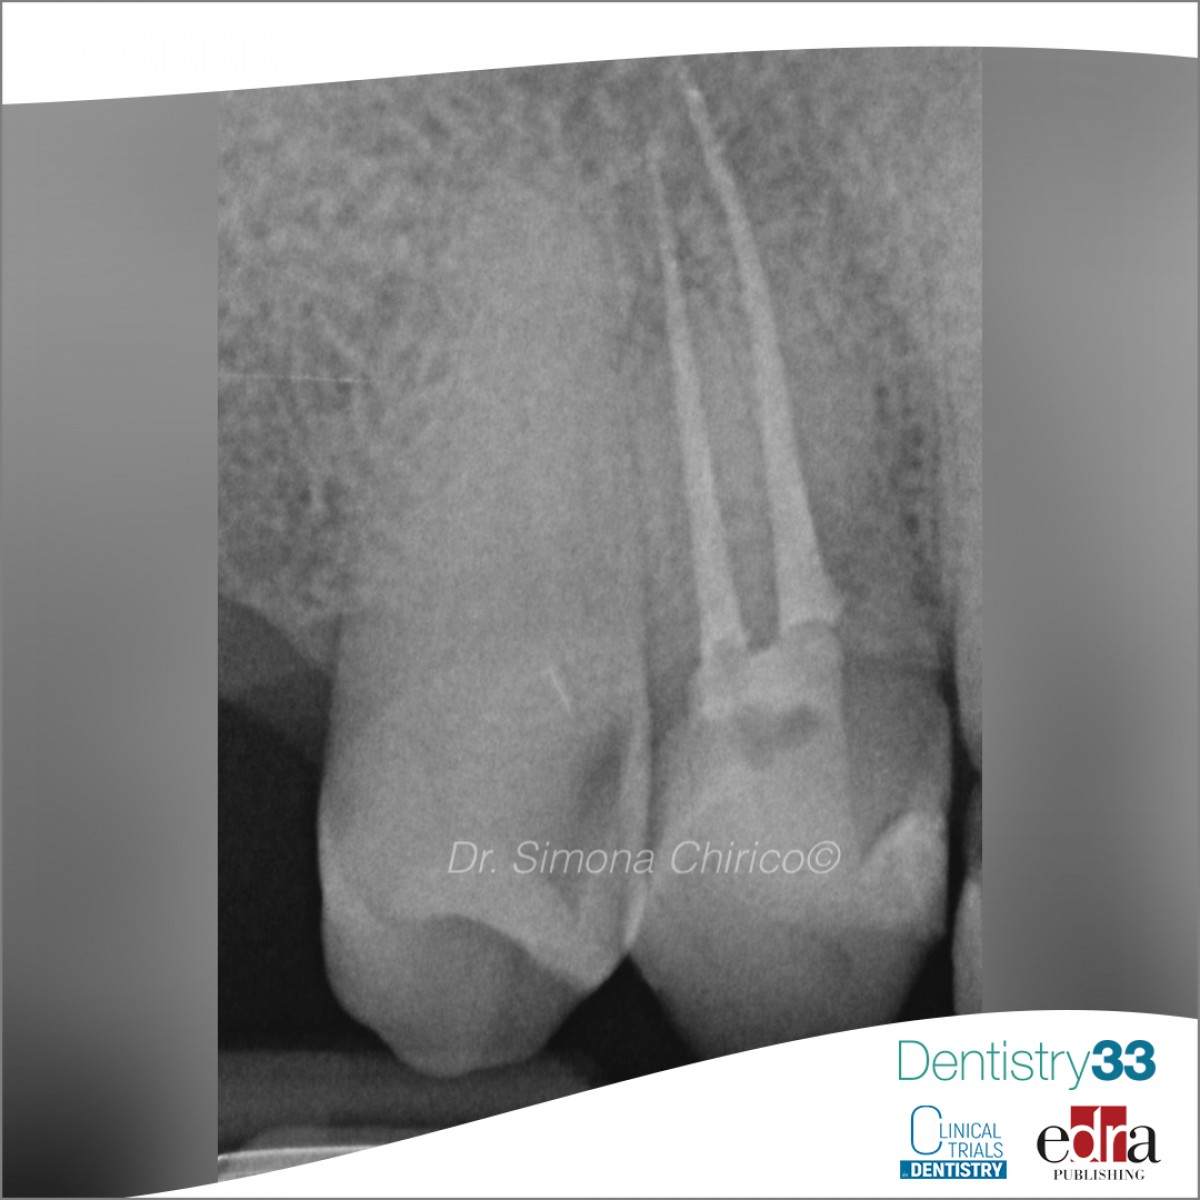

None of the teeth responded positively to thermal or electrical tests, although the sensitivity to palpation was observed in 4 cases and to percussion in 2 cases. Radiographic examination, which included a periapical radiograph (Kodak RVG 6100; Carestream Health, Rochester, NY) and a selective CBCT scan (Newtom 5GXL; Newtom, Verona, Italy), revealed an apical lesion in 6 of the 7 teeth and PCO advanced in all teeth. Surgical planning software (BlueskyPlan, Libertyville, IL) was used to design the 3D guides which were then printed and proper fit occurred. The endodontic treatment was then carried out under isolation with a rubber dam, and the design of the access cavity was carried out. Working length was determined using an apex locator (Raypex 5; VDW, Munich, Germany) and digital radiography. The root canal shaping was performed using the ProTaper Next system (Dentsply Maillefer, Baillagues, Switzerland) or WaveOne Gold instruments (Dentsply Maillefer) under irrigation with 5.25% sodium hypochlorite. In 2 teeth, calcium hydroxide was left for 3 weeks as there was uncontrollable suppuration in the first session. All root canals were sealed with hot gutta-percha using the continuous wave technique. No patient reported discomfort on percussion or palpation 1 year after treatment if periapical healing was evident.